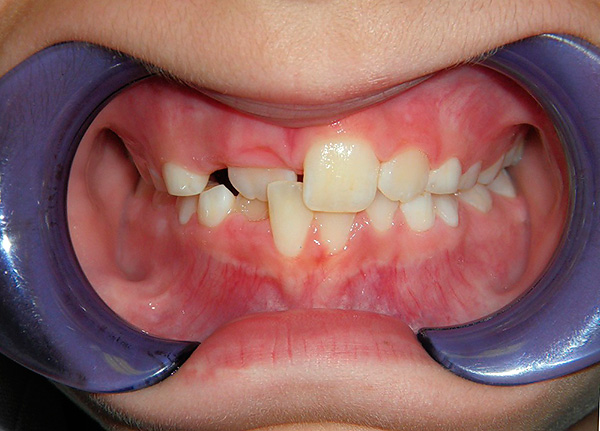

- Anquilose e artrite da ATM. A anquilose é uma fusão patológica dos elementos da articulação entre si, o que no nosso caso limita a mobilidade da mandíbula. Esse processo pode ser o resultado de artrite prolongada, ou seja, um processo inflamatório ou o resultado de uma lesão - por exemplo, resultante da aplicação de pinças durante os cuidados obstétricos. O tratamento da anquilose é geralmente muito trabalhoso e requer tratamento ortodôntico a longo prazo em uma equipe com um cirurgião maxilofacial. Às vezes, o tratamento leva 10 anos ou mais, respectivamente, e a mordida cruzada será corrigida gradualmente à medida que o paciente envelhece. Um exemplo de um paciente com anquilose é mostrado na foto abaixo:

- Violações do tempo e da sequência da dentição. Cada dente deve entrar em erupção normalmente na dentição para determinar o tempo e o local especificado para esse dente. Se, por exemplo, um dente não entrar em erupção por um longo período de tempo por algum motivo, os dentes existentes geralmente se movem para preencher um vazio (compensar um defeito na dentição) - como resultado, são criados contatos patológicos, razão pela qual o desenvolvimento de uma mordida cruzada.E se os dentes entrarem em erupção muito mais tarde, quando a dentição já estiver formada, os “camaradas tardios” terão que literalmente encontrar um lugar para si. Por exemplo, um dente pode cortar as dobras transitórias das gengivas, na direção dos lábios, bochechas ou palato;